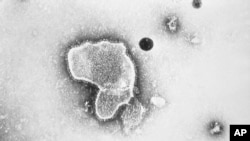

Children’s hospitals in parts of the United States are reporting a worrying surge in respiratory syncytial virus, or RSV.

The common virus affects the breathing system, usually causing minor sickness like a runny nose and cough. But RSV infections can cause much more serious disease in babies and old people.